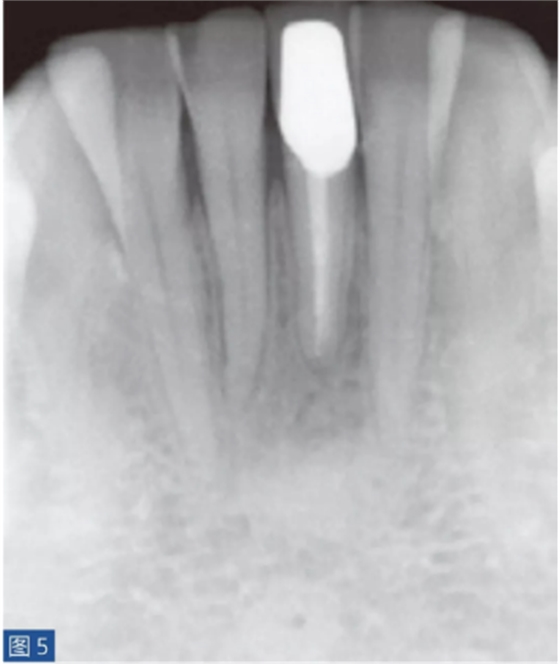

牙齒無(wú)癥狀的根尖周炎(圖4 和5)是由牙髓壞死引起的,并且通常是在癥狀性根尖周炎之后發(fā)生。因此,對(duì)冷、熱刺激和牙髓電活力測(cè)試無(wú)反應(yīng)。叩診無(wú)或者引起輕微的疼痛。如果骨皮質(zhì)已經(jīng)發(fā)生改變并且涉及到口腔軟組織,則觸診可引起輕微不適。放射學(xué)檢查,可能出現(xiàn)硬骨板不連續(xù)(破壞)以及根尖周和牙間組織的廣泛性破壞。

圖4:31 牙齒AAP。術(shù)前X線片?;颊咴V叩診和觸診時(shí)有輕微疼痛。

圖5:31 牙齒AAP。根管再治療12 個(gè)月后。